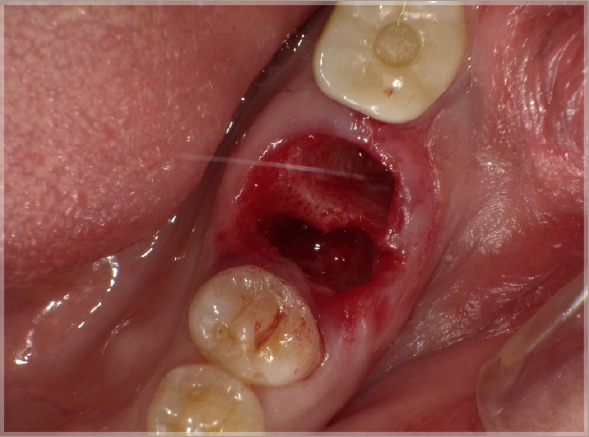

1.折れた歯を抜歯します

①破折線確認

②抜歯